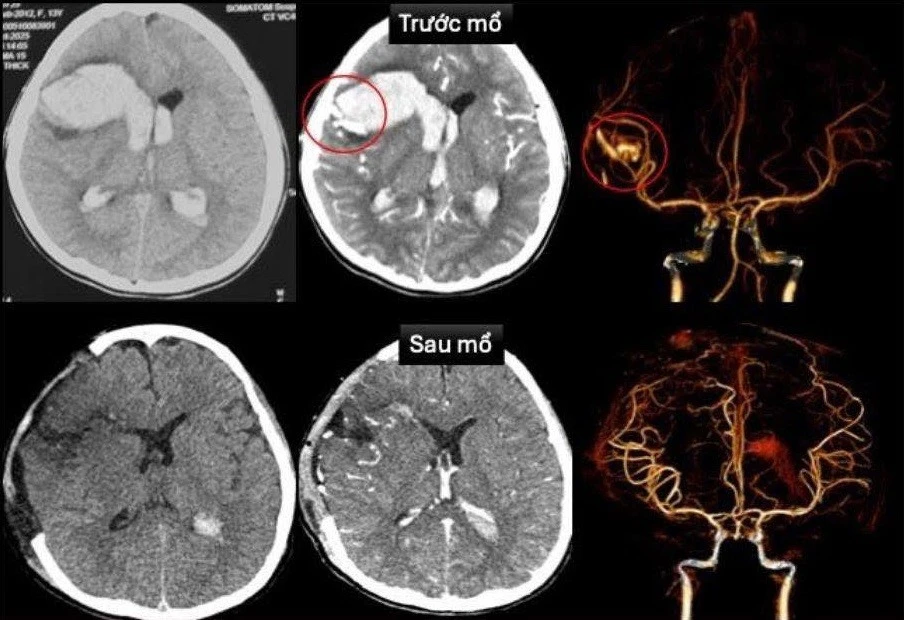

TPO - Nhập viện sau khi đột ngột hôn mê sâu, các bác sĩ xác định bệnh nhi bị vỡ dị dạng mạch máu não, biến chứng nặng trên nền bệnh cơ tim xốp. Đây là bệnh lý tim hiếm gặp, rất nguy hiểm ở trẻ em.